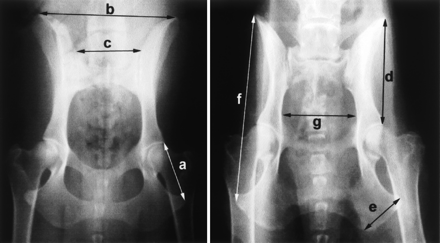

Figure 2.

Hip X-rays from two size-matched dogs at opposite extremes of the PC4 axis of variation. Individual metrics are indicated: a, ischium; b, ilium span; c, sacrum; d, ilium; e, ischial tuberosity; f, oscoxa; and g, pelvic inlet. The differences in pelvic shape are presented schematicallyin Figure 1.